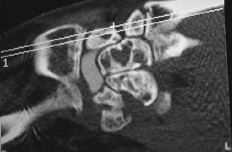

ABFigura 6. Imágenes líticas intraóseas de predominio hueso grande-piramidal. A: Radiológica. B: Tomografía computerizada.

La sinovitis ocasiona también la aparición de quistes en los huesos carpianos vecinos, principalmente el hueso grande y el piramidal,9,19,26,43,44,47 porque la sinovial es capaz de penetrar por los defectos corticales e invadir la zona menos resistente del hueso esponjoso formando un nidus. Habitualmente se encuentran partículas de silicona en el contenido de los quistes y en la sinovial.43 Asimismo, estas partículas se han encontrado en los nódulos linfáticos regionales por migración a través del sistema linfático. Sin embargo, las autopsias en humanos y en animales después de un amplio período de tiempo con un implante de silicona no muestran evidencia de mutación celular ni de diseminación sistémica de las partículas a órganos a distancia.19,43

Debido a esta falta del implante hemos observado en un 20% de los casos luxación y subluxación de la artroplastia, en un 30% inestabilidad en DISI y en un 10% en VISI. La incidencia de imágenes líticas intraóseas y sinovitis por liberación de partículas de silicona en nuestra serie es del 40%. Surgen por la abrasión y el desgaste del implante y producen una sinovitis hipertrófica con granulomas por silicona.19 Microscópicamente se aprecia la respuesta del huésped a estas partículas como una reacción de células gigantes a cuerpo extraño. Los leucocitos y macrófagos fagocitan el material, pero la silicona no se afecta por las enzimas lisosomales, lo que induce una sinovitis reactiva que no es exclusiva de la silicona (PMMA, polietileno y otros materiales metálicos), estando siempre en relación con el tamaño de la partícula. Las partículas de silicona son de 30 a 60 micras de diámetro. Estos implantes se han desaconsejado para la sustitución del escafoides y del semilunar, ya que al estar sometidos a importantes cargas de compresión se produce su fragmentación.31 Los factores que desgastan el implante de silicona y contribuyen a la formación de partículas son las fuerzas excesivas a través del implante debidas a la asociación de inestabilidad o de colapso, una malposición o exceso de tamaño, exceso de movilidad y abuso de la actividad diaria.43,44